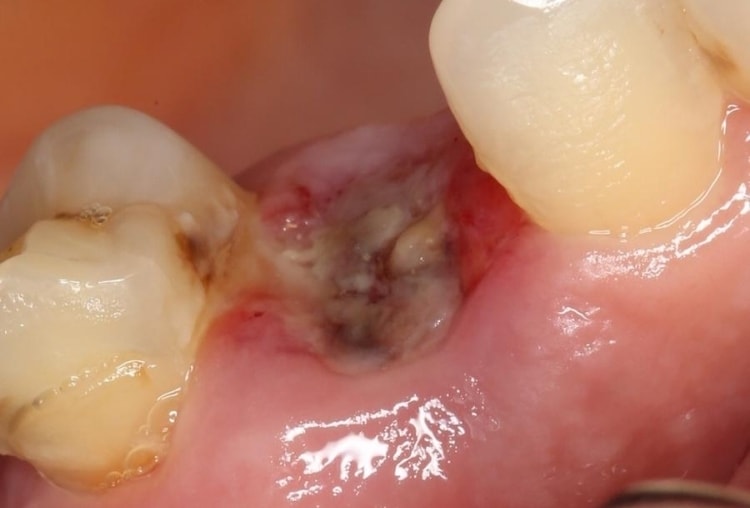

К диагностическим критериям альвеолита относятся медленное затягивание лунки, и появление интенсивного болевого синдрома на 3-5 сутки. Хронический процесс выявляется стоматологом во время осмотра. Лунка лишена грануляций, т. е. совершенно пустая, а на ее дне нередко просматриваются костные структуры.

Покраснение десны, содержимое в виде остатков рыхлого сгустка крови, частичек пищи, слюны в ране, что лунка «сухая», в разгаре воспаления: отечную красную слизистую по краям лунки, болезненность при касании, на стенках серый или желтоватый налет.